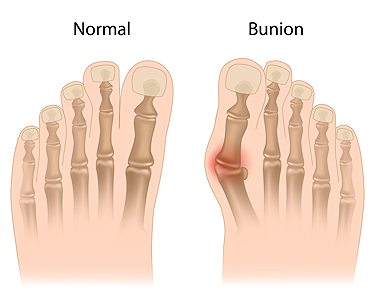

Various Types of Bunions

What Is a Bunion?

Bunions are painful bony bumps that usually develop on the inside of the foot at the joint of the big toe. As the deformity increases over time, it may become painful to walk and wear shoes. Women are more likely to exacerbate existing bunions since they often wear tight, narrow shoes that shift their toes together. Bunion pain can be relieved by wearing wider shoes with enough room for the toes.

Bunions

A bunion is an enlargement of the base joint of the toe that connects to the foot, often formed from a bony growth or a patch of swollen tissues. It is caused by the inward shifting of the bones in the big toe, toward the other toes of the foot. This shift can cause a serious amount of pain and discomfort. The area around the big toe can become inflamed, red, and painful.

Bunions are most commonly formed in people who are already genetically predisposed to them or other kinds of bone displacements. Existing bunions can be worsened by wearing improperly fitting shoes. Trying to cram your feet into high heels or running or walking in a way that causes too much stress on the feet can exacerbate bunion development. High heels not only push the big toe inward, but shift one's body weight and center of gravity towards the edge of the feet and toes, expediting bone displacement.

A podiatrist knowledgeable in foot structure and biomechanics will be able to quickly diagnose bunions. Bunions must be distinguished from gout or arthritic conditions, so blood tests may be necessary. The podiatrist may order a radiological exam to provide an image of the bone structure. If the x-ray demonstrates an enlargement of the joint near the base of the toe and a shifting toward the smaller toes, this is indicative of a bunion.